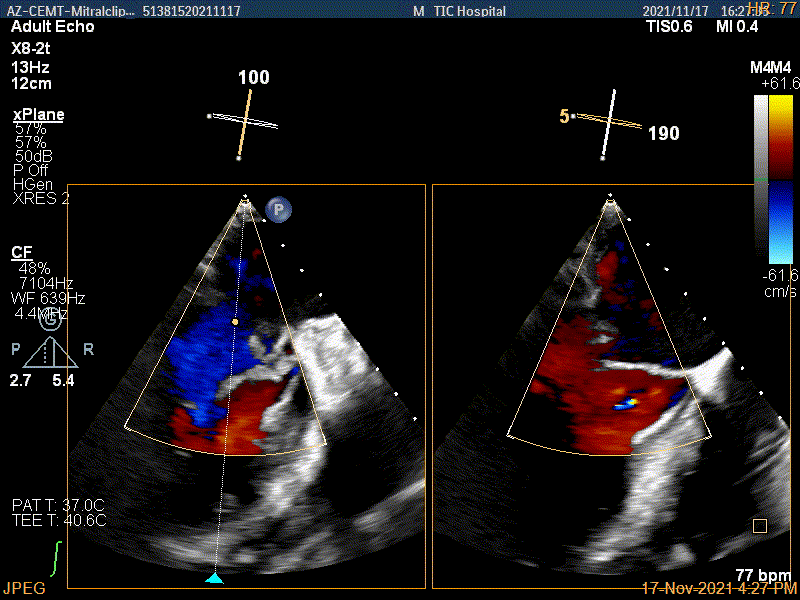

X-plane:下夹子尝试捕获靠近AC区脱垂瓣叶

3D证实夹子内侧残余脱垂(P1区)

3Dcolor证实残余分流主要来源于残余脱垂